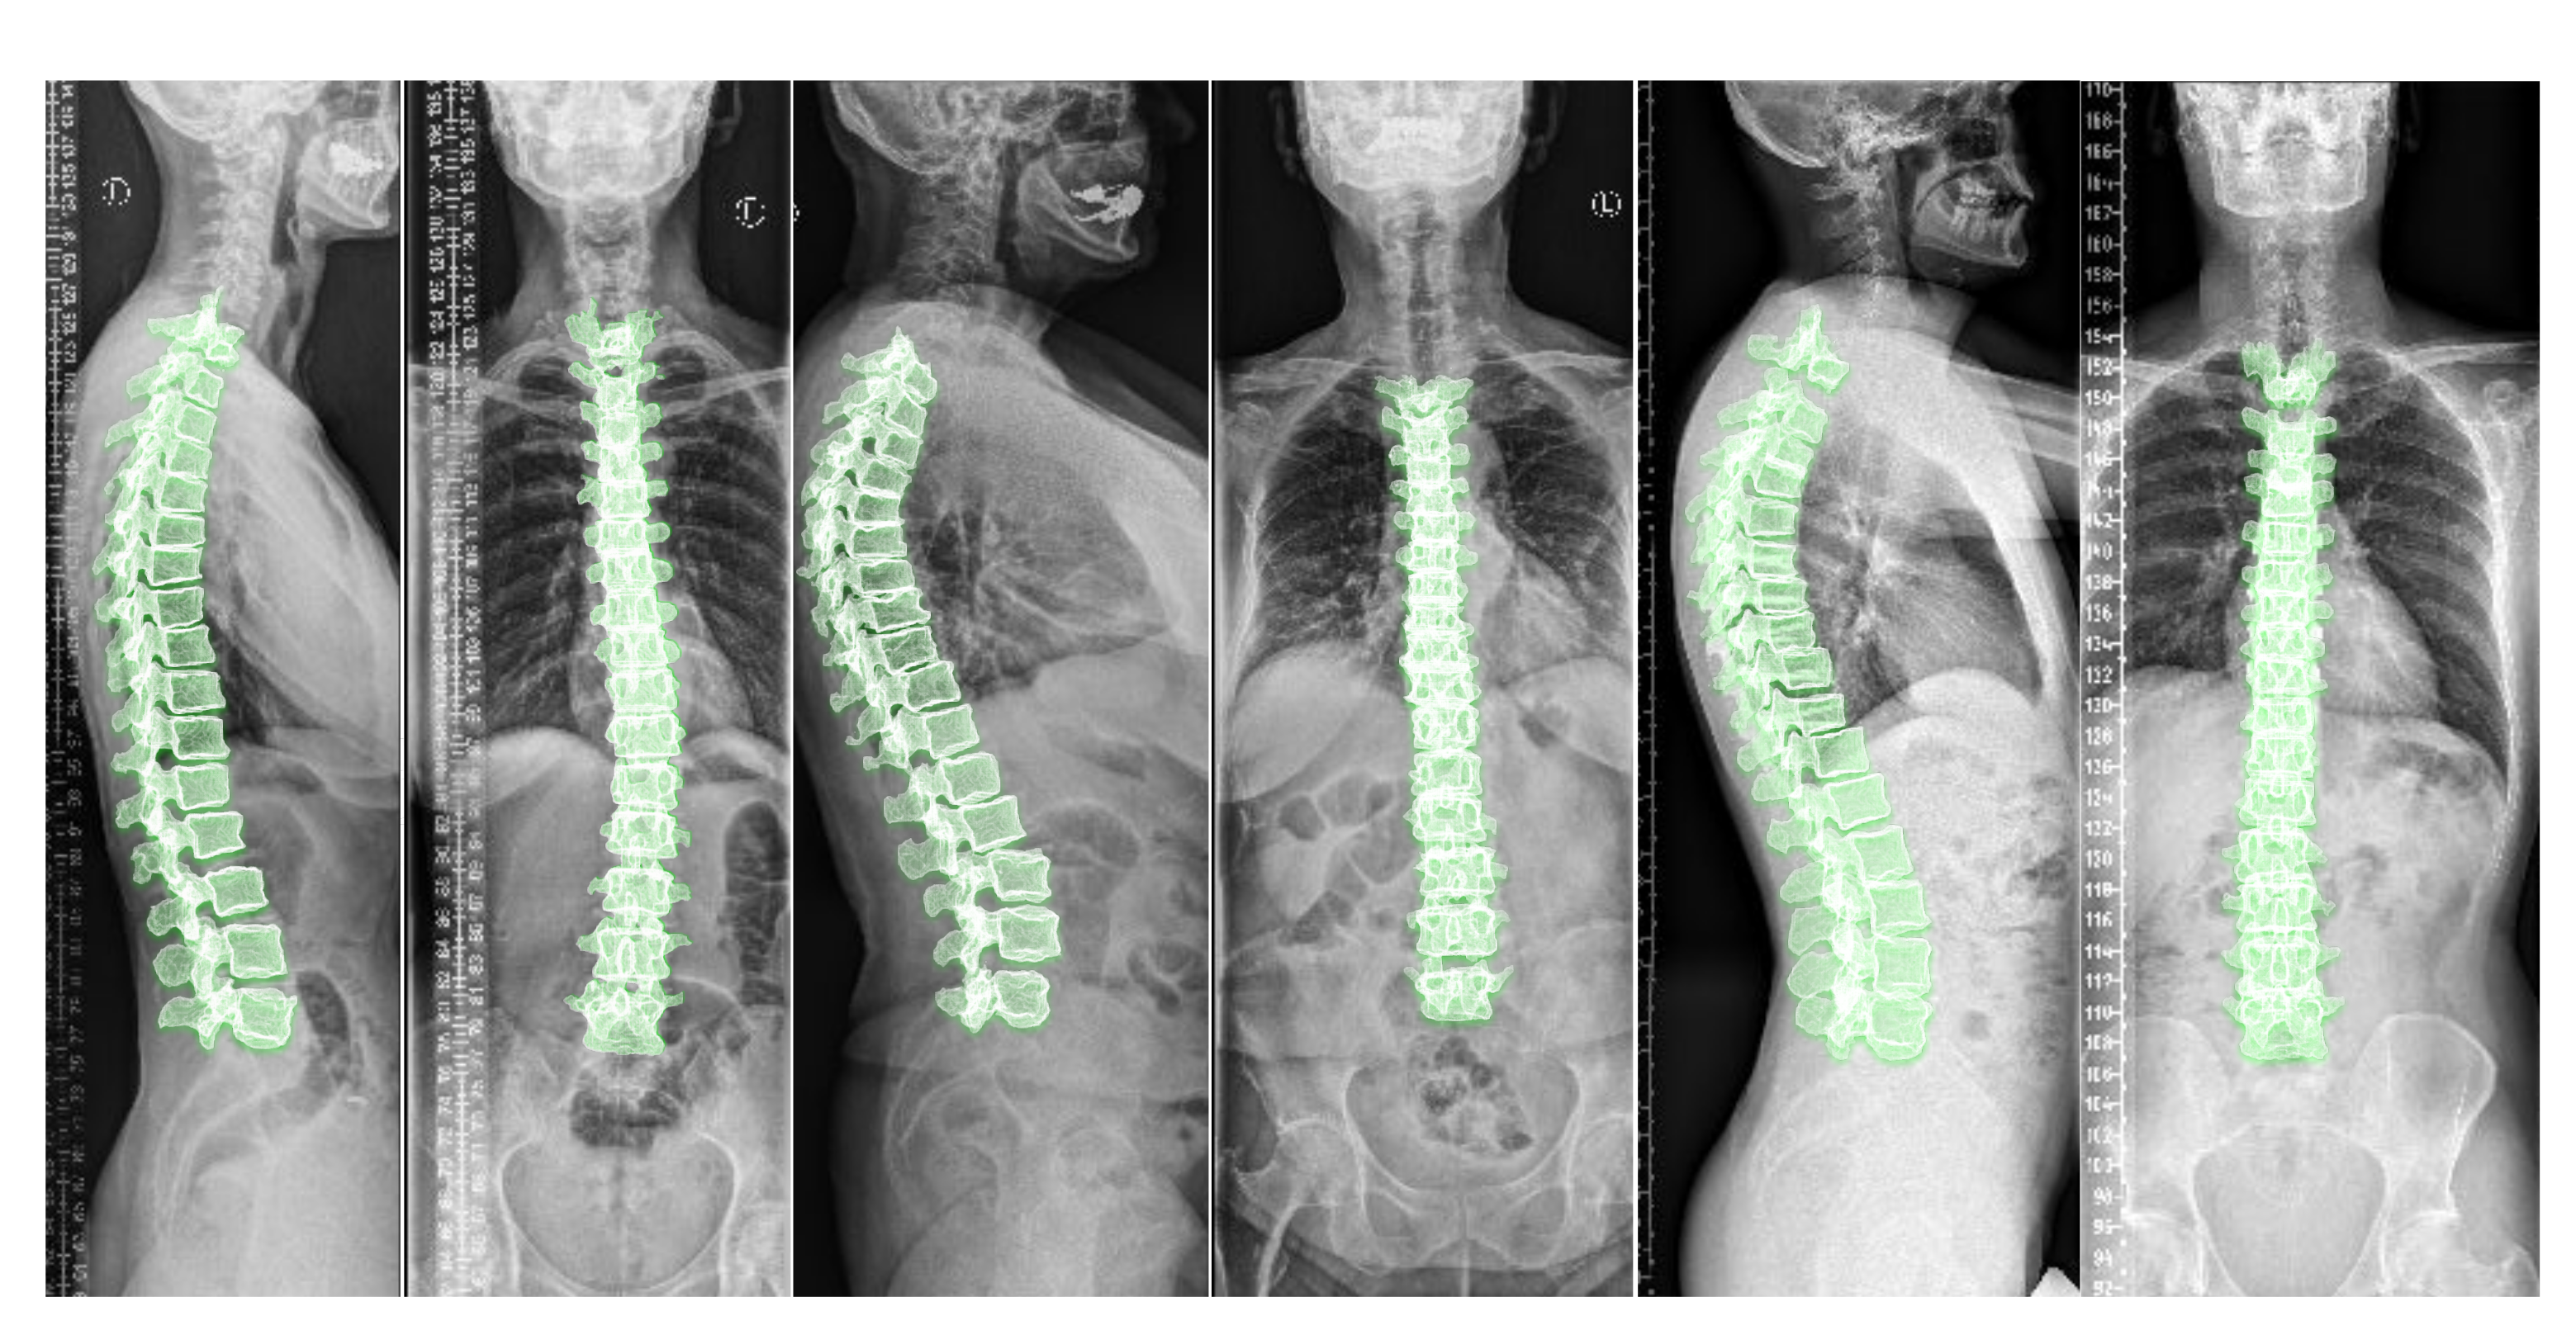

A biomechanical load analysis of the spine in an upright standing position is highly warranted in various spine disorders to understand their cause and guide therapy [1]. Typical approaches for load estimation either use a computational shape model of the spine for all patients or obtain a subject-specific spine model from a 3D imaging modality such as magnetic resonance imaging (MRI) or computed tomography (CT) [2]. Even though MRI and CT images can capture 3D anatomical information, they need the patient to be in a prone or supine position (lying flat on a table) during imaging. Nevertheless, to analyze the spinal alignment in a physiologically upright standing position under weight bearing, orthogonal 2D plain radiographs (as depicted in Figure 1) are the de facto choice. A combination of both these worlds is of clinical interest to fully assess the true biomechanical situation, that is, to capture the patient-specific complex pathological spinal arrangement in a standing position with full 3D information [2,3,4].

Including the vertebral centroid coordinates in the global coordinate system provides the model with a holistic shape of the spine. For example, Figure 1 demonstrates lateral and anterior–posterior (AP) view radiographs of three different patients. The distance between the centroids determines the scale. If one fits a curve to all of the vertebral centroids, the orientation of each vertebra should be almost perpendicular to the curve at each vertebral centroid. Although defining the orientation of the vertebrae and the other constraints, such as inter-vertebral distance, needs accurate vertebral landmark detection on radiographs, we postulate a Multi Layer Perceptron (MLP) which estimates the 3D affine parameters, given only the vertebral centroids and the information extracted by the encoders.

Figure 1. Lateral and anterior-posterior (AP) view radiographs of three patients with spinal curvature annotation. Considering the vertebral centroid coordinates and spinal curvature facilitates determining the scale and the vertebral orientation.